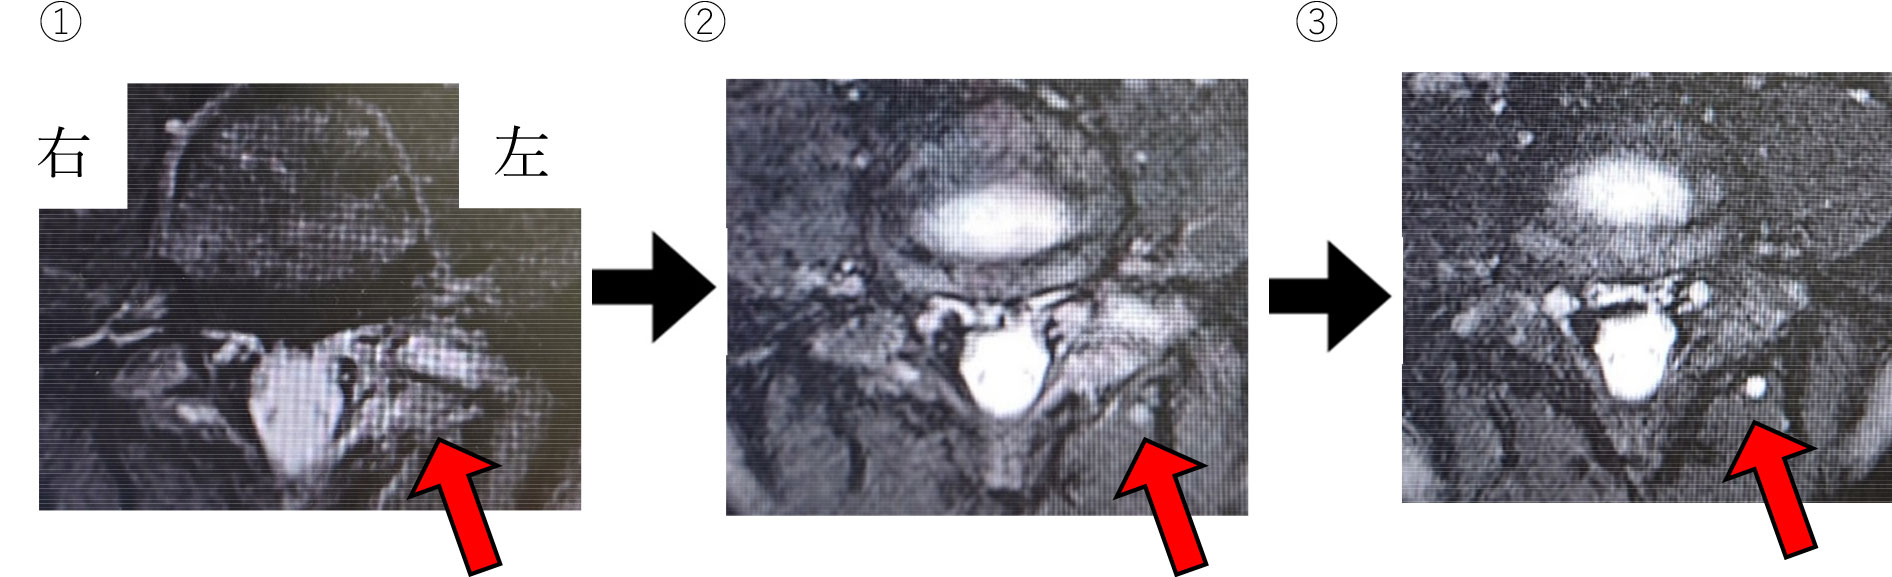

画像での変化(自験例)を見てみましょう。

MRI(STIR)

- ①初期:骨髄浮腫がみられる。

- ②1か月後:より明確な骨髄浮腫がみられる。

- ③4か月後:骨髄浮腫が軽減してきている。

(赤矢印の白くみえる部分が骨髄浮腫。逆側の正常部分は黒くみえます。)